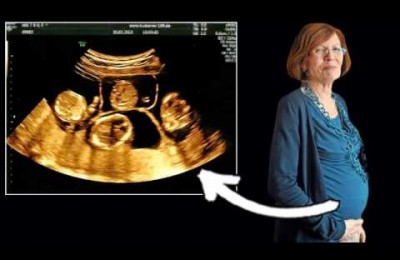

Una mujer alemana de 65 años con 13 hijos da a luz a cuatrillizos

Una portavoz del hospital ha señalado que los bebés tienen una gran posibilidad de supervivencia pero puede que tengan complicaciones ya que no se han desarrollado...